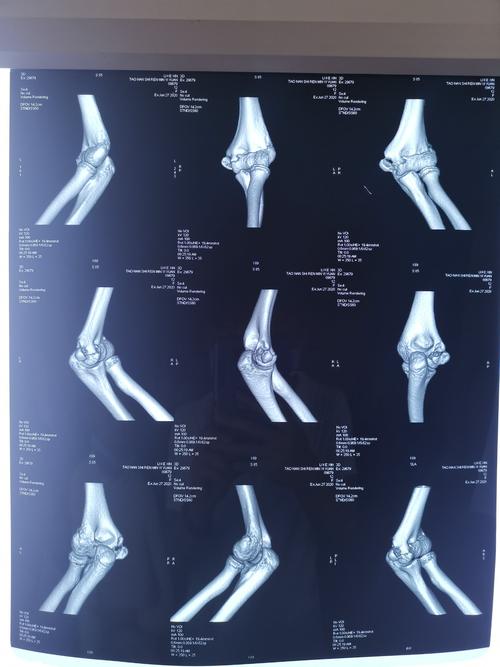

术后石膏固定35天,现患者左侧肘关节活动受限,关节活动度伸-屈:45-135

肘关节片子正常图

肘关节正常x光片

肘关节拍片正常图

正常肘关节x光片图片

肘关节正侧位片图片